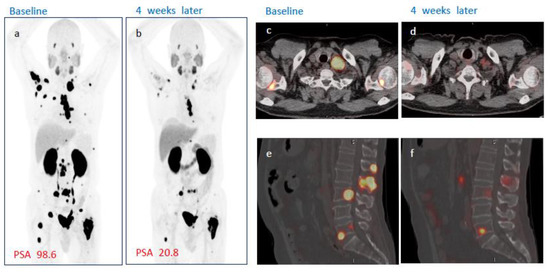

3.5. Radiological Assessment